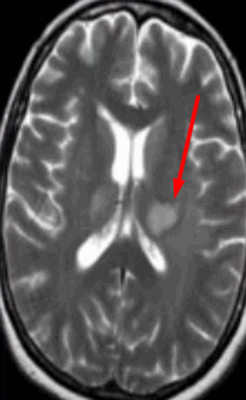

Признаки атеросклероза (пораженные участки указаны стрелками) на МРТ

Изменение липидного метаболизма приводит к появлению в крови нерастворимых жиров - холестерина. Вещество откладывается на стенках сосудов в виде пятен, которые со временем утолщаются и прорастают соединительной тканью. Данный процесс носит название липосклероз.

Холестериновые отложения постепенно накапливают соли кальция. Бляшка приобретает твердость, выпячивается в просвет сосуда, деформируя стенку в месте прикрепления. Атерокальциноз увеличивает риск образования тромбов.

Холестериновая бляшка сужает просвет артерии, нарушает ток крови, вызывает ишемические явления в тканях. При нестабильности возможен отрыв патологического образования и облитерация (закрытие) сосуда.